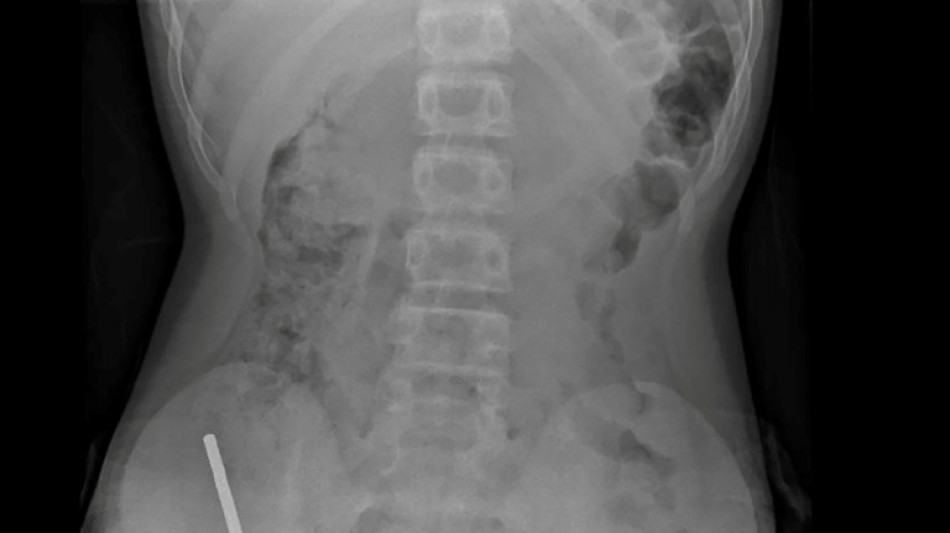

Nouvelle-Zélande: un adolescent opéré après avoir ingéré près de 100 aimants achetés sur Temu / Photo: Handout - NEW ZEALAND MEDICAL JOURNAL (NZMDJ)/AFP

"Il avoué avoir ingéré entre 80 et 100 aimants puissants au néodyme, de 5x2mm environ, une semaine plus tôt", indique un rapport des médecins de l'hôpital de cet hôpital, publié dans le New Zealand Medical Journal (NZMJ).

Les médecins ont déclaré que la pression exercée par les aimants avait provoqué une nécrose dans quatre zones de l'intestin grêle et du gros intestin du garçon.